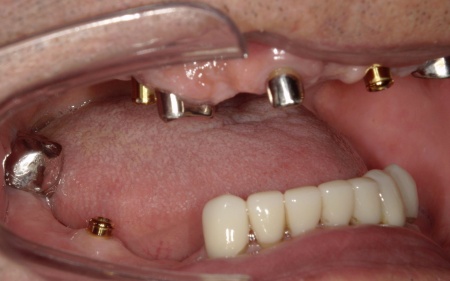

拝見したところ、すでに複数の歯が欠損しており、上下顎には入れ歯が装着されていました。

上前歯は、装着していたブリッジ(複数の人工歯を連結した被せ物)が外れてしまっているため、食事や会話に大きな支障をきたしています。

次に、上下左右の奥歯部に1本ずつ、左上前歯に1本、計5本のインプラントを埋入する手術を行いました。

根管治療が終了した上の歯には、オーバーデンチャーの支えとなる内冠(入れ歯を安定させるための土台)を、インプラント部分にはロケーター(義歯をしっかり固定するための連結装置)を装着しました。